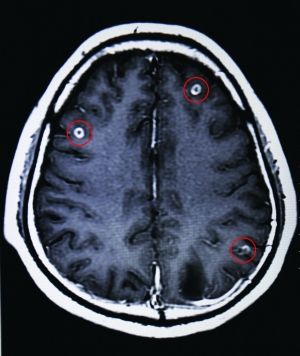

紅圈處為該青年腦中部分寄生蟲

2月18日,省二醫接診了一位來自廣西的青年,該病人稱自己經常頭暈無力,看不清東西。經掃描發現,該青年大腦中竟盤踞著19條寄生蟲。

據省二醫門診部王主任介紹,此病叫做“腦囊蟲病”,多見于青壯年——吃了豬肉中的豬肉絳蟲蟲卵,經消化道進入腸壁再進入腸系膜靜脈,最后經血液循環將蟲卵送到腦膜、腦實質以及腦室內。而患病青年也承認自己喜歡生吃豬血。

王主任告訴記者,此病雖不是什么疑難雜癥,且也不難醫治,發病初期僅靠藥物就可得到控制。但患病如不及時治療,腦組織及大腦中樞則易受損,進而引起頭疼、無力、肢體運動障礙癥狀,嚴重的會引發癲癇,視物不清,失明甚至死亡。